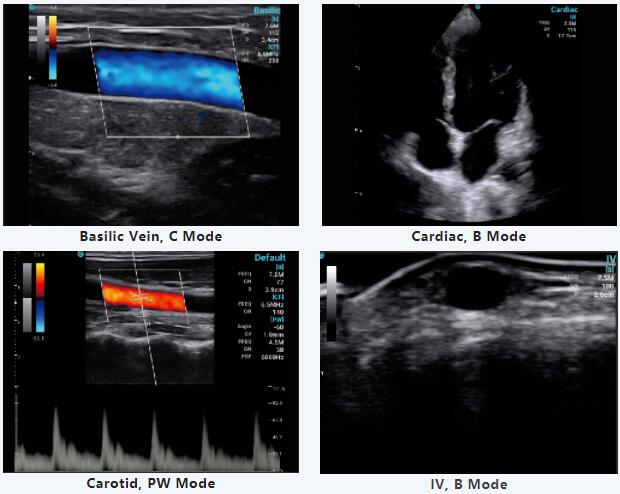

En este seminario web especial, el Dr. Jerome compartió una parte de su trabajo diario utilizando CHISON SonoEye; según su video, estamos profundamente impresionados con la portabilidad de SonoEye y su diagnóstico preciso, y descubrimos lo útil que podría ser SonoEye en las aplicaciones clínicas.

Además, el Dr. Jerome compartió con las funciones innovadoras de SonoEye e hizo un análisis completo y valioso del mercado del ultrasonido portátil. La importancia y la demanda de ultrasonidos portátiles seguirán aumentando, haciendo que la atención médica de primera calidad esté al alcance de la mano.